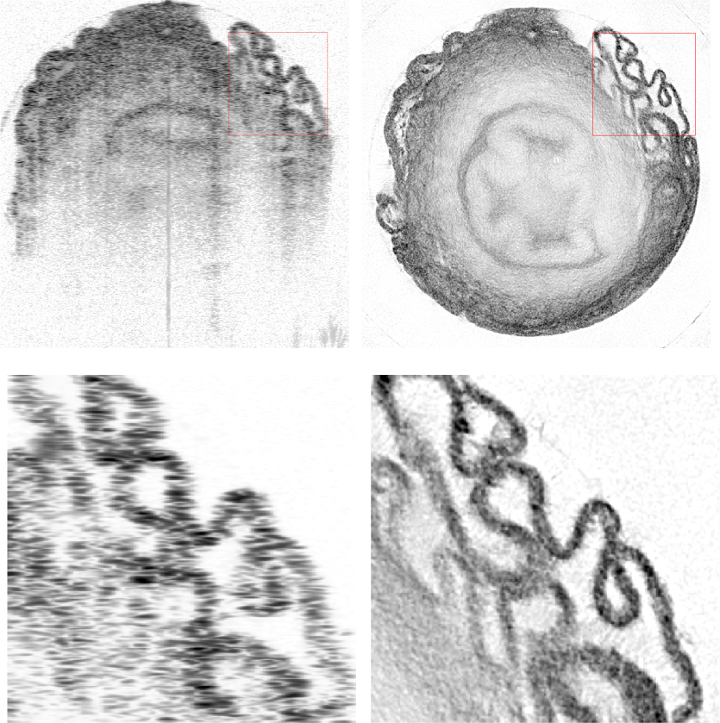

In the research team's paper that describes the work, Izatt and his doctoral student, Kevin Zhou, take a different approach. Rather than relying on holography, the researchers combine OCT images acquired from multiple angles to extend the depth resolution to the lateral dimension. Each individual OCT image, however, becomes distorted by the light’s refraction through irregularities in the cells and other tissue components. To compensate for these altered paths when compiling the final images, the researchers needed to accurately model how the light is bent as it passes through the sample.

For these proof-of-concept experiments, Zhou took tissue samples such as the bladder or trachea of a mouse, placed them in a tube, and rotated the samples 360° beneath an OCT scanner. The algorithm created a map of each sample’s refractive index, increasing the lateral resolution of the scan by more than 300% while reducing the background noise in the final image. While the study used samples already removed from the body, the researchers believe OCRT can be adapted to work in a living organism.